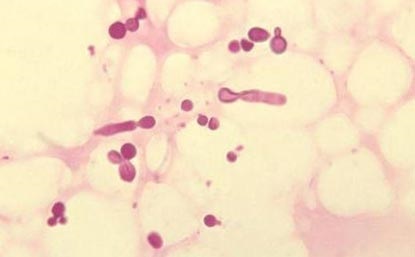

Fig. 4. Bacteriile care populează gura: mutanții Streptococcus (verde). Bakteroides gingivalis, cauzând periodontita (lila). Candida albicus (galben).

Fig. 8. Ciuperci din genul Candida (Candida albicans). Ei în mod constant din momentul nașterii, sunt paraziți pe piele și membranele mucoase, fără a provoca boli. Prin reducerea imunității și utilizarea ineptă a larg spectru antibiotice provoacă infecții fungice la leziuni slab definite la organele interne, pune viața în pericol.